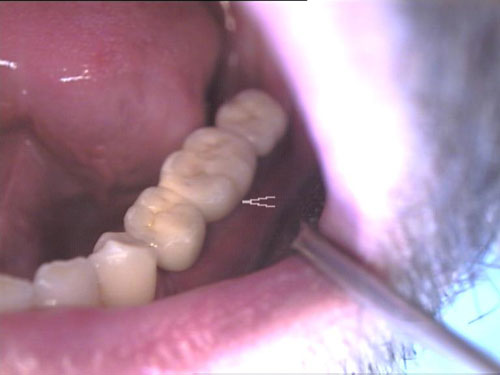

Brückenersatz

Keramikkrone 1

Keramikkrone 2